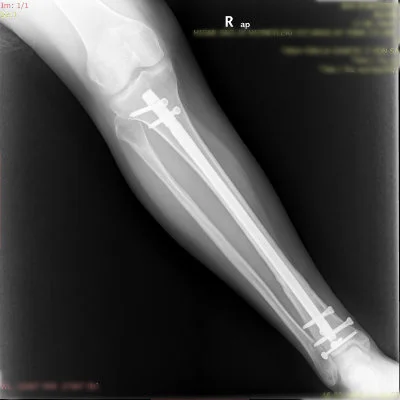

Görüntüleri büyütmek için resmin üstüne tıklayınız.